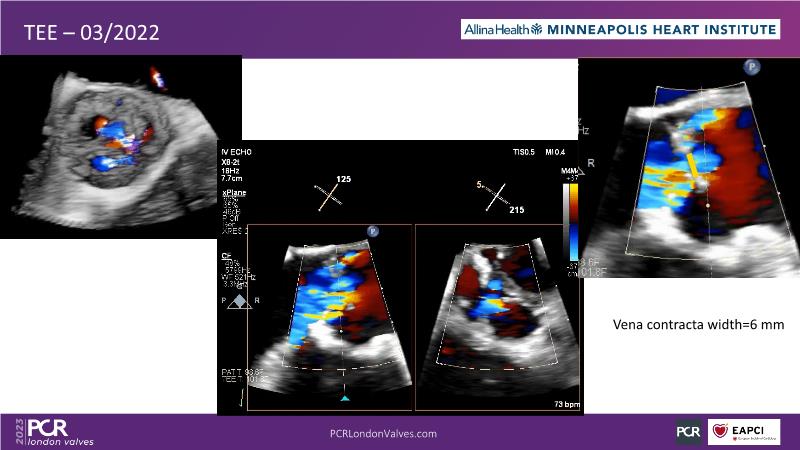

- To understand the challenges of imaging for aortic regurgitation and how it can lead to underdiagnosis